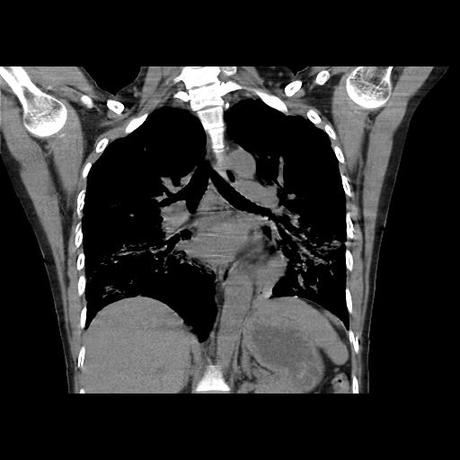

Se realiza volumen de tórax en fase simple, desde los opérculos torácicos hasta los hemidiafragmas, observándose:

El parénquima pulmonar con areas parcheadas difusas en vidrio despulido combinadas con otras areas hipodensas de baja atenuación debidas a atrapamiento aéreo y engrosamiento intersticial y zonas de fibrosis de predominio en lóbulos medios e inferiores de ambos pulmones.

- LOS HALLAZGOS PUEDEN ESTAR EN RELACIÓN A NEUMOPATIA INTERSTICIAL PROBABLE ETIOLOGIA HIPERSENSITIVA VS AUTOINMUNE/BACTERIANA/FUNGICA.